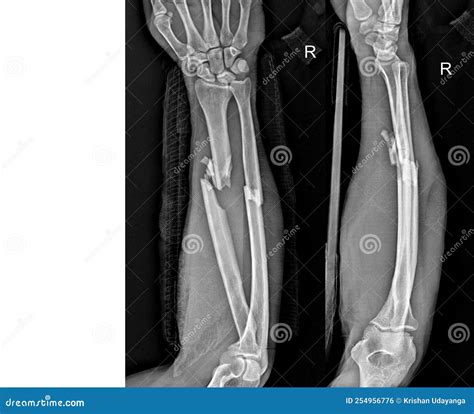

Fractured Radius Ulna

Diagnosing a fractured radius ulna involves a combination of physical examination and imaging tests. The diagnostic process typically includes:

• X-Rays: X-rays are the primary imaging tool used to confirm the presence and severity of a fracture. They provide detailed images of the bones and can show the exact location and type of fracture.

• Open Reduction and Internal Fixation (ORIF): This procedure involves realigning the broken bones and securing them with plates, screws, or rods.